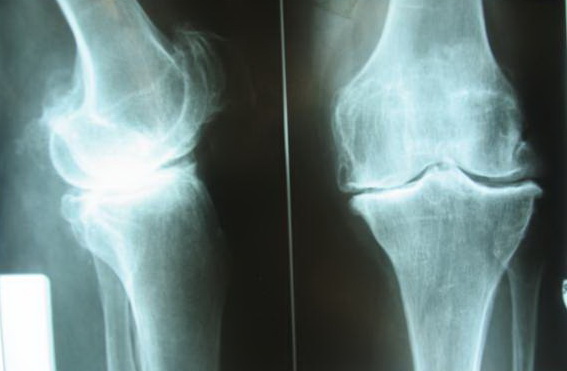

Корригирующая остеотомия как лечение артроза без эндопротезирования

Появилась боль в паху, бедре или колене и не только не проходит, а постепенно усиливается. Человек идёт в поликлинику, ему делают рентгенографию сустава и выявляют «артроз». Что делать дальше? К сожалению, как правило, больному назначают консервативное лечение (таблетки, уколы, мази) независимо от степени артроза и он годами лечится без особого эффекта, начинает искать какие-то нетрадиционные методы лечения («китайская медицина», народные целители и т.п.). И только настрадавшись и потратив кучу денег, когда становится совсем плохо, боль беспокоит постоянно и человек уже не может ходить, он обращается к ортопеду. А ведь можно было избежать этих ненужных страданий и материальных затрат, обратись человек к специалисту сразу после установки диагноза «артроз».

На сегодняшний день общепризнано, что эндопротезирование тазобедренного и коленного суставов является единственным эффективным методом лечения при разрушении суставного хряща и позволяет избавит пациента от боли и вернуть его к активной жизни. В мире ежегодно выполняется более полутора миллионов таких операций. Современные эндопротезы служат десятки лет и позволяют жить полноценной жизнью даже молодым и активным пациентам, а в случае, если эндопротез всё же износился, его можно заменить на более сложный и продолжать пользоваться всеми благами жизни.